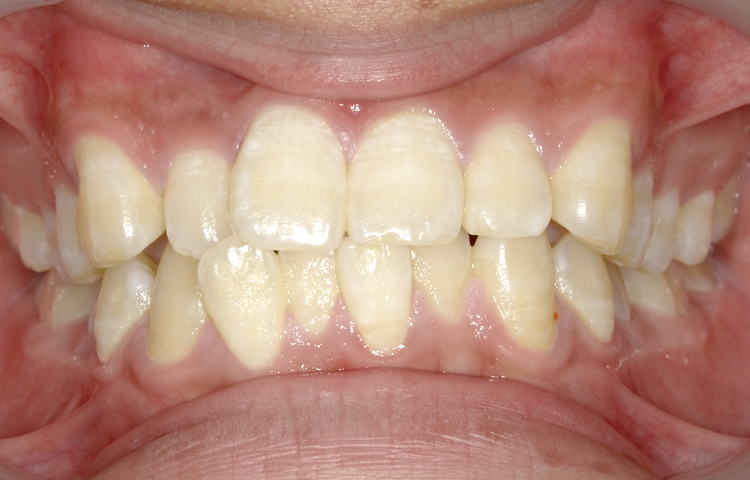

症例3

治療前

治療後

| 主訴 | 上下前歯全体の歯並びが気になる |

|---|---|

| 治療 期間 |

約6ヶ月 |

| 治療費 | 330,000円(税込)/調整費用別途 |

| 治療 内容 |

上下の前歯部にワイヤーを着けて進めていく、プチ矯正で施術。 |

| 治療の リスク |

固定の装置をつけないと後戻りしてしまう。 |